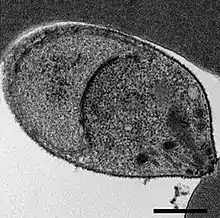

![]() مسحاتٌ مصبوغةٌ بصبغة جيمزا لمُتصورةٍ نُّولسيَّة أصابت خلايا دم حمراء بشرية | |

تُشّخص الملاريا عادةً عبر فحص اللطاخات الدموية المصبوغة بصبغة جيمزا تحت المجهر، ولكن على الرغم من هذا، إلا أنَّ التمييز بين المتصورة النولسية والأنواع الأخرى من المتصورة يُمثل تحديًا؛ وذلك نظرًا لتشابهها مظهريًا.[12] تكون طفيليات المتصورة النولسية في الدَّور الحلقي عند صبغها بصبغة جميزا مشابهةً لطفيليات المتصورة المنجلية في دورها الحلقي، حيث تظهر على شكل دائرةٍ تحتوي نقطة أو نقطتين داكنتين من الكروماتين.[18] تكون الأتاريف (جمع أتروفة) القديمة أكثر تشتتًا، وتشكل شكلًا مستطيلًا منتشرًا عبر الخلية المُضيفة يُسمى "شكل النطاق"، ويشبه نفس الدور في المتصورة الوبالية الملارية.[18] تظهر النقاط خلال هذا الدور أحيانًا عبر خلايا الدم الحمراء المضيفة، وتسمى "تنقيط سينتون وموليغانز".[18] تظهر المتقسمات (جمع متقسمة) بشكلٍ مشابهٍ لأنواع المتصورة الأخرى، حيث تكون على شكل مجموعاتٍ من الأقاسيم الأرجوانية المُحاطة بصبغة مركزية داكنة اللون.[18]